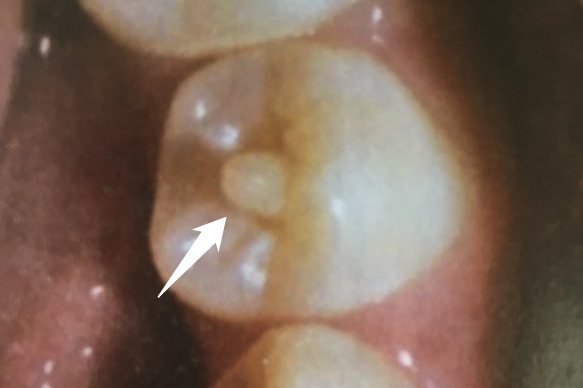

畸形中央尖基底部直径约2mm,游离端尖细,或为圆顿,或为结节状。高低不等,一般1-3mm.结构不一,大部分由釉质组成,中央部为薄层牙本质,并有髓角突入。当牙尖磨损或折断后,可见底部的环状痕迹,颜色较深的中心为突入到中心的髓角或形成的继发牙本质。一般无临床症状,常在口腔检查时偶然发现,多数患者是在中央尖折断并发牙髓和根尖周炎症后就诊。